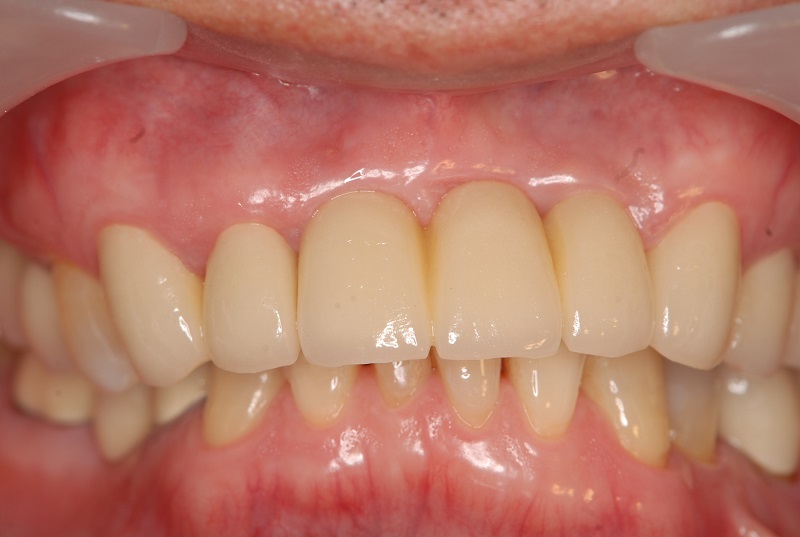

症例4【60代女性】臼歯部が崩壊して奥歯で物が噛めない

治療前

治療後

主訴 下顎臼歯部のインプラント周囲炎を併発している。又、上顎臼歯部においては歯周病が進行しており、咀嚼ができない状態である。インプラント周囲炎に関しては、インプラント体を撤去し力学的に安定した位置に1本のみ埋入。

上顎は、臼歯部に採血で得られるCGFメンブレンとAFG(人工骨β―TCPとAFGを混ぜたブロック)を併用したソケットリフト(骨造成)を行い、

インプラントを4本埋入。オペから仮歯を経て最終補綴物ジルコニア装着まで約5カ月を要した。

リスクとしては、ソケットリフト(骨造成)による一過性の副鼻腔炎が起きる可能性がある。まれに洞底膜が破れる可能性がある。

ただし、膜は約3週で再生するので、膜の回復を待ち、再オペを行う。

費用 276万(オペ・ソケットリフト・人工骨・採血による濃縮血小板生成・仮歯・最終補綴物まで含む)